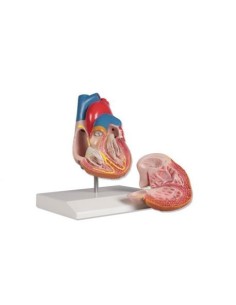

Du crâne en 22 parties à verrouillage magnétique aux modèles de colonne vertébrale, des modèles d'articulation aux modèles de cœur, chaque pièce de notre collection est conçue pour une immersion totale dans l'étude de l'anatomie humaine. Nos modèles, réalisés à partir de scans d'os réels, garantissent une expérience tactile authentique et une fidélité de poids presque identique aux originaux.

Indispensables aux étudiants comme aux professionnels, nos modèles anatomiques sont des outils pédagogiques qui permettent d'observer les structures anatomiques avec précision, en évitant les dissections ou les études invasives. Ils sont également utiles pour expliquer les pathologies aux patients, ce qui rend la communication plus efficace et permet de gagner un temps précieux.